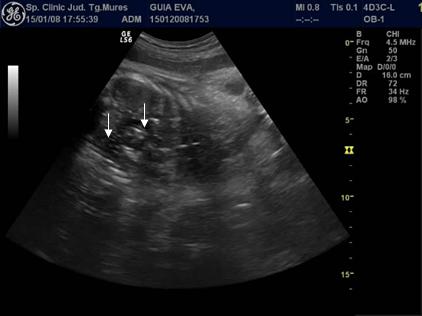

Fig. nr. 239 Aparitia de bule in cavitatile toracica si abdominala ( sageti ), dupa maceratie la fatul mort intrauterin , la 34 sapt.

Fig nr. 240.

Edem tegumentar al coapsei ( sageata ) aparut la maceratie, aceeasi sarcina ca

in figurile anterioare